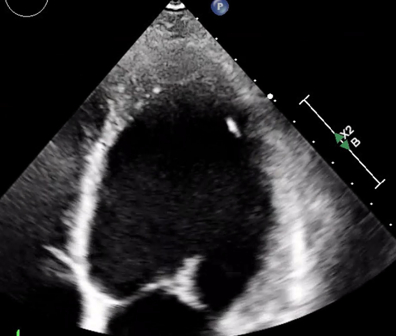

A 28-year-old G2P1 woman presented at 27 weeks gestation with progressive dyspnea and lower extremity edema. She was found to have atrial fibrillation and flutter with RVR. Initial TTE revealed severely dilated left ventricle (LV) with reduced systolic function (EF 20-25%) (Figure 1). She remained in flutter despite diuresis, rate control with metoprolol and digoxin, cardioversion, and ablation. Initiation of guideline-directed medical therapy was limited by hypotension and pregnancy. She underwent a cesarean section at 32 weeks given ongoing arrhythmia and heart failure symptoms. Skin fragility and poor uterine tone were noted intraoperatively. This, in addition to her exam findings of arachnodactyly and hypertelorism, prompted genetic testing, which was positive for SMAD3 mutation consistent with Loeys-Dietz syndrome (LDS) type 3. Following delivery, spironolactone and enalapril were added in keeping with breastfeeding compatibility. Her arrhythmia burden continued to lessen. Repeat TTE showed EF of 35-40% and normal LV size. MRA of head to pelvis was notable for mild dilation of intrarenal abdominal aorta (2.5 cm) with no other vascular abnormalities.